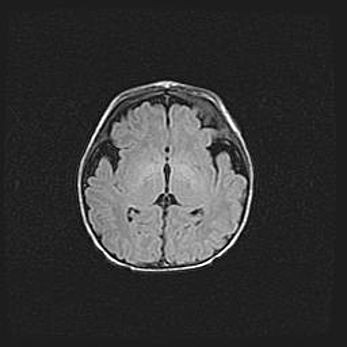

Церебральная ишемия II.

Возраст: 5 дней

Вес: 3400 г

Пол: женский

Окружность головы: 35 см

Срок гестации: 39 недель

Церебральная ишемия – это заболевание, характеризующееся недостаточностью (гипоксией) либо полным прекращением (аноксией) снабжения мозга кислородом по причине закупорки одного или нескольких сосудов. Это приводит к  что метаболическим расстройствам различной степени тяжести в тканях головного мозга, развитию коагуляционных некрозов и гибели нейронов.